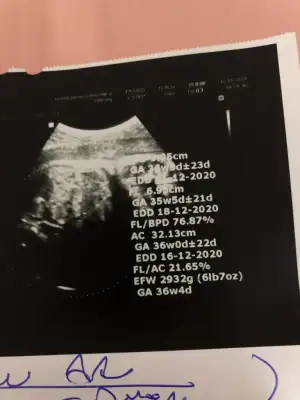

Oyyy kuzum derdimiz bu olsun ben hiç takmadım kızım 35 cm doğdu be büyümedi şuan 4 yaş ama maşallah 7 yaş boya sahipUltrason ölçümlerinde mm kaydırma kısa veya uzun çıkabiliyormuş

Ben çok kafama taktım artık Allahtan ne gelirse saldım gitti bi kısa dedi çocuğuma bi hiç bişi demediBanu Çiftçi videolarında boy ölçümü kafanızda ortalama bişi oluşsun diye söylenir hiçbir zaman net rakam değildir diyor

Benimkine iki hafta önce 44 cm demişti 47 cm doğsun öpüp başıma koyacağım

Önemli olan sağlıcakla doğsun miniklerimiz. Doktora demedim bile iki hafta önce 49 du diye